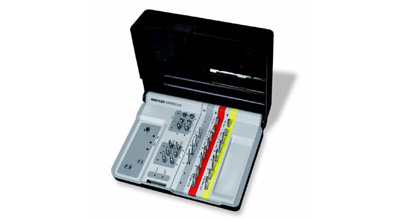

Разные производители по-разному подходят к формированию набора инструментов. Так, например, компания Dentium выпускает два отдельных набора, один для хирургов:

другой — для протезирования:

Другие компании-производители включают компоненты для протезирования (как минимум, для временного) в хирургический набор. Обычно это делают для систем, предназначенных для немедленной имплантации и т. н. «немедленной нагрузки». Такими являются, например, XiVE:

или Ankylos, который композиционно очень на него похож:

разумеется, это влечет за собой увеличение количества инструментов и усложнение хирургического набора: